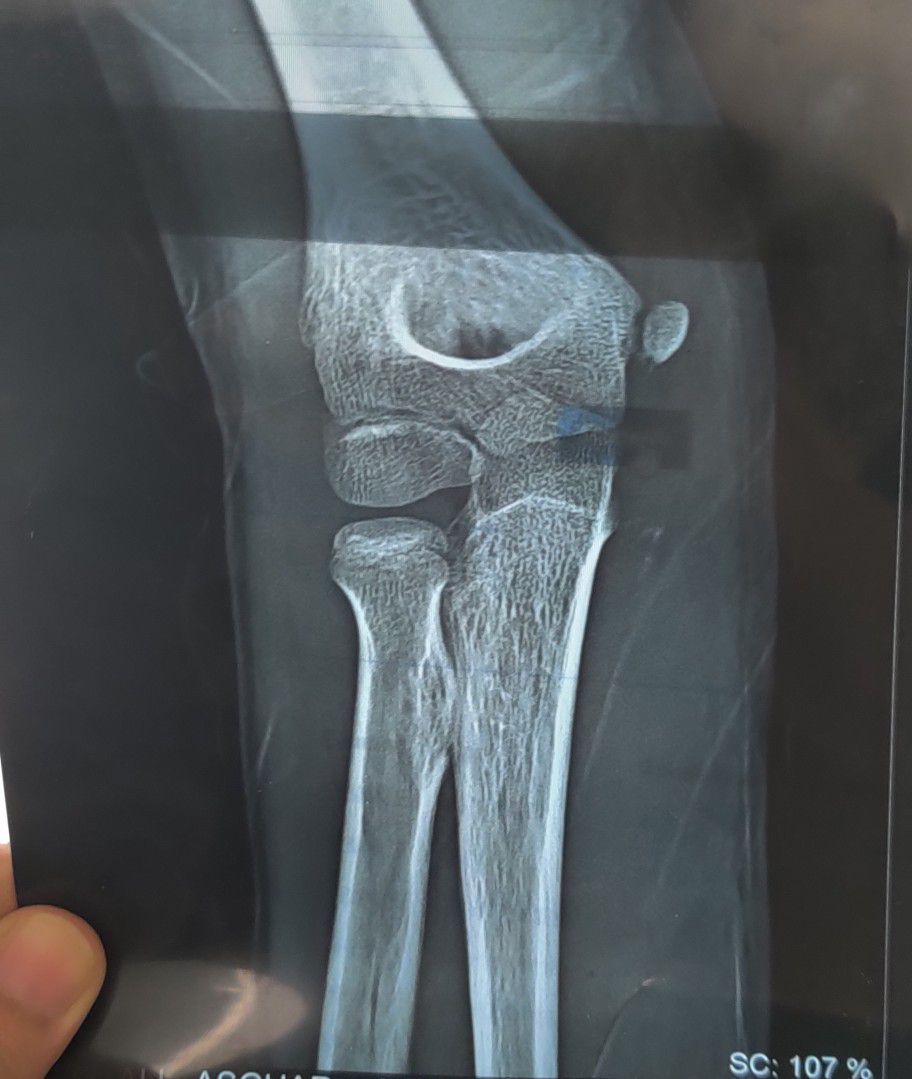

X-ray of an elbow in a 10 year old boy with the history of fall. Can you spot any finding?

Orthopaedics

Elbow

Fall